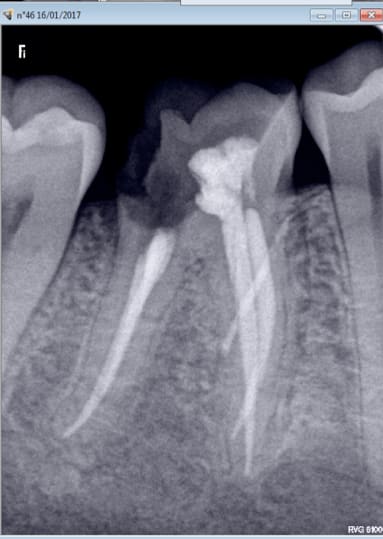

Concernant l'utilisation, je ne me suis pas fait à la sensation, selon les patients çà va rentrer comme dans du beurre en 2 seconde, ou au contraire çà ne bougera pas d'un poil au bout d'une minute avec fracture de 3 aiguilles (En même temps la radio me montrait la corticale la plus blanche que j'ai jamais vue sur 3 millimètres dans ce cas spécifique, j'aurais du m'en douter; je vous laisse deviner l'origine ethnique du patient).

>En même temps la radio me montrait la corticale la plus blanche que j'ai jamais vue sur 3 millimètres dans ce cas spécifique, j'aurais du m'en douter; je vous laisse deviner l'origine ethnique du patient).<

L'examen tres attentif de la radio est indispensable avant une QS, donnant en effet par la couleur dominante de l'os alveloaire son degré de trabéculation, et le point d'attaque; se mefier ainsi de deux racines tres rapprochées. La palpation est aussi importante, on a mentalement une image 3D de la zone a perforer. L'implantologue fait pareil pour son exercice.

Oui évidemment. Mais autant on peut gérer l'axe et le point d'insertion pour esquiver les racines, autant pour l'épaisseur de la corticale il n'y a pas grand chose à faire une fois qu'on a choisi l'aiguille appropriée. Si çà ne passe pas, çà ne passe pas.

La 46 je ne pense pas que c'est un canal accessoire. Technique de thermo

compaction efficace. J'ai pas de mal à trouver les canaux beaucoup plus à trouver de l'os meuble -))))